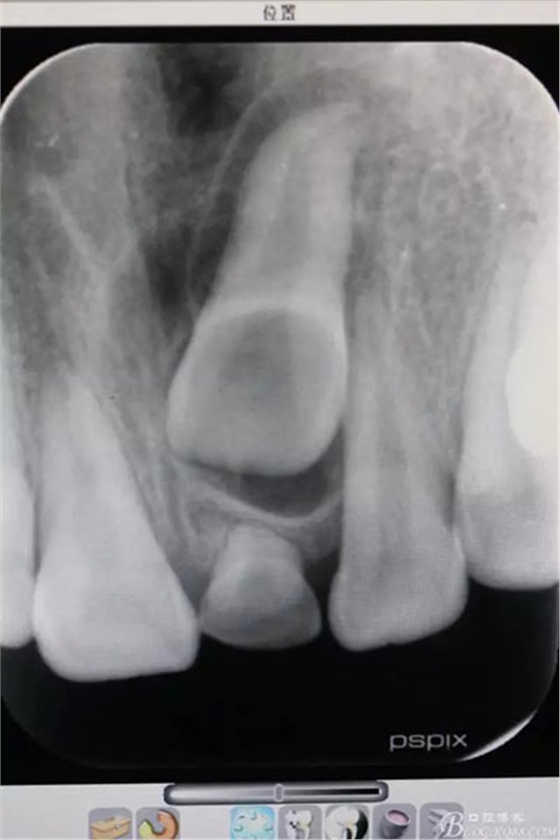

圖1.術(shù)前根尖片影像檢查:21根尖1/3彎曲,牙冠上方有一致密團(tuán)塊影。左乳Ⅰ滯留

圖20.術(shù)后的根尖片影像檢查:21移動約 3mm距離,牙冠方向基本正常,半年后復(fù)查,定正畸治療方案